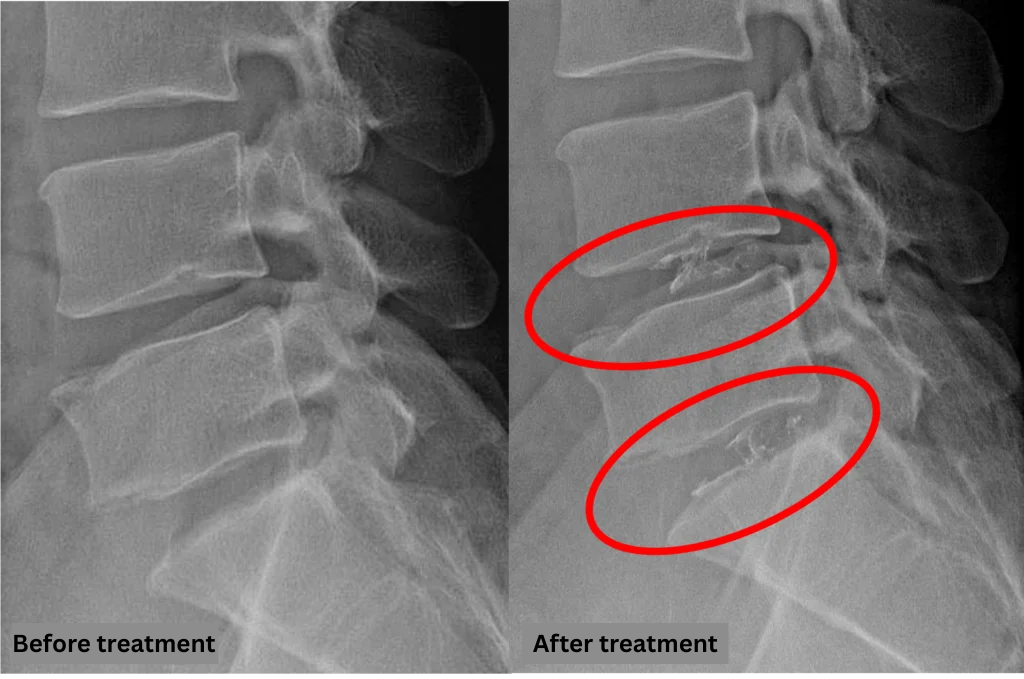

- L4/5, L5/S: Disc degeneration and lumbar disc herniation

The above findings were also observed on the imaging.

These findings suggest that compression of the spinal canal due to disc pathology at L4/5 and L5/S is highly likely to be the cause of symptoms.

After consulting with the patient, the Cellgel Method was performed on L4/5 and 5/s.